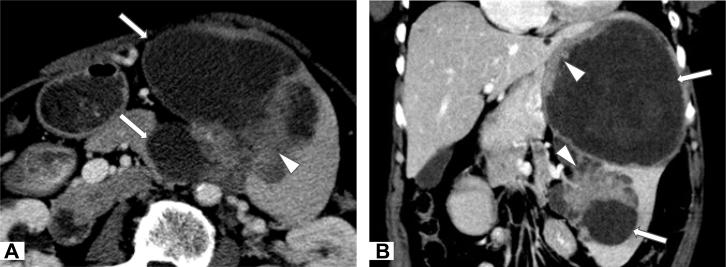

The commonly seen primary malignant neoplasms of the spleen are angiosarcoma and lymphoma. We present a case of serous cystadenocarcinoma of the spleen. It was presumed to be originated from dropped nonmalignant ovarian tissue, which was accidentally implanted to the splenic surface during hysterectomy and bilateral salpingooophorectomies for torsion of right fallopian tube 9 and half years ago and transformed into serous cystadenocarcinoma later. Computed tomography demonstrated a multilocular predominantly cystic tumor with internal soft tissue components in the spleen.

脾脏常见的原发性恶性肿瘤是血管肉瘤和淋巴瘤。我们报告一例脾脏浆液性囊腺癌。据推测,它起源于脱落的非恶性卵巢组织,该组织在9年半前因右侧输卵管扭转行子宫切除术和双侧输卵管卵巢切除术中意外植入脾脏表面,后来转变为浆液性囊腺癌。计算机断层扫描显示脾脏有一个多房性、以囊性为主的肿瘤,内部有软组织成分。